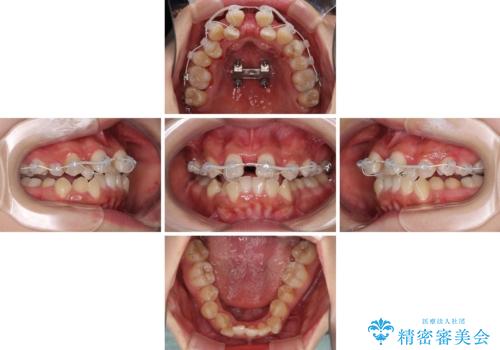

前後に重なった前歯 ワイヤー装置と急速拡大装置を併用したインビザライン矯正

急速拡大装置による上顎骨の側方拡大が思った以上にうまくいき、非抜歯での矯正が可能となりました。

内側に倒れていた下顎の臼歯は起き上がり、清掃性も大幅に改善されました。